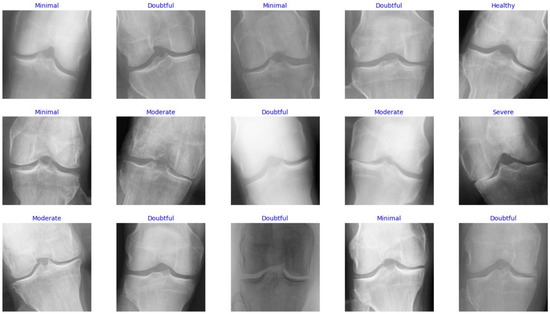

In this study, the Knee Osteoarthritis Severity Grading dataset is used to train and evaluate the performance of the proposed model. It contains knee X-ray images for OA detection and KL grading. Five gradings constitute the dataset labels as follows: healthy knee image (grade 0), doubtful joint space narrowing (JSN) with possible OA (grade 1 or healthy), confirmed OA and possible joint space narrowing (grade 2 or minimal), multiple moderate OA with confirmed JSN and mild sclerosis (grade 3 or moderate), and large OA with significant JSN and severe sclerosis (grade 4 or severe). The data are distributed based on the grades, such that there are 604 images for grade 0, 275 images for grade 1, 403 files for grade 2, 200 images for grade 3, and 44 images for grade 4. Figure 2 shows samples of images with various labels.

From the data distribution illustrated above, it can be seen that the dataset has a class imbalance, which might lead to classification bias toward the majority label. To mitigate this drawback, data augmentation was used to balance the training set so that each class contains 500 samples. Several techniques were employed to conduct the augmentation, including flipping, rotation, shifting, and zooming. Table 2 shows the augmentation parameter customization used in this study, which was determined experimentally.